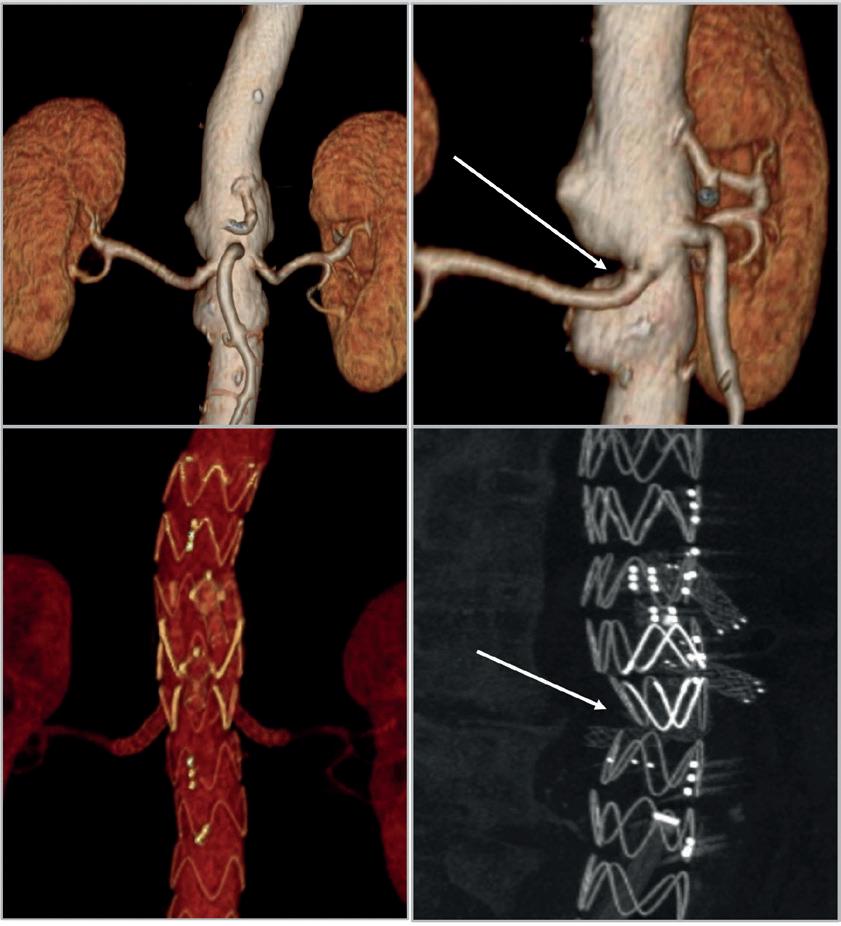

Michele Piazza (Padua, Italy) advises how to manage the challenging anatomical scenario of a narrow aorta during fenestrated and branched endovascular aneurysm repair (F/BEVAR), highlighting accurate, patientspecific planning and use of the correct bridging stent technology as the keys to good results.

For more on this story go to page 21.

First indicated & dedicated platform for bridging stents in FEVAR

Precise & standardised positioning due to a dedicated fenestration marker

2-in-1 design that combines inflation & flaring in one step